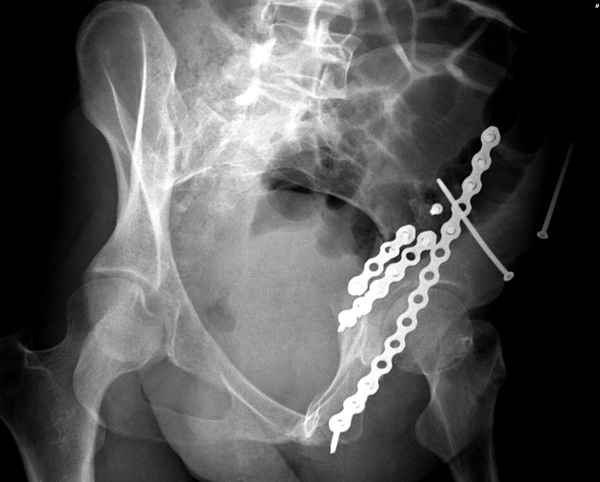

высылаю дополнительно сканы.

Когда перелом не получается отнести к какому либо типу - эффективнее всего описать более детально. В дальнейшем проще бывает сортировать, и что важнее - "руководство к действию" бывает более обоснованным. В данном случае графа клинического диагноза может выглядеть так: Застарелый разрыв правого крестцово-подвздошного сочленения, консолидирующиеся со смещением переломы крыла и тела правой подвздошной кости, обеих колонн и задней гемисферы правой вертлужной впадины. Состояние после остеосинтеза.

>Застарелый разрыв правого крестцово-подвздошного сочленения, консолидирующиеся со смещением переломы крыла и тела правой подвздошной кости, обеих колонн и задней гемисферы правой вертлужной впадины. Состояние после остеосинтеза.

Судя по представленным реконструкциям (не очень хорошего качества - много наводок)

мы имеем дело с полупоперечным переломом у которого отломался задний край или его отломали, превратив перелом в полный двухколонный.

По отдельным срезам и тем более по реконструкции трудно судить о сращении крыла и задней колонны с осевым скелетом.

В большинстве случаев при двухколонных переломах

в итоге получается прочный бублик с дыркой. При эндопротезировании в дырку помещается головка, а чашка должна неплохо заклиниться в бублике.

Главное, чтобы бублик не был разорван, что не очень понятно на представленных снимках.

Из того минимума, что представлено, мне кажется, мы имеем дело с двухколонным переломом вертлужной впадины. Обычно медиальный (центральный) "вывих" головки встречаются в сложных двухколонных переломах со смещением.

По-моему, надо готовить больного к будущей артропластике, но без опоры на задний столб невозможно удержать протез. Опорная конструкция (кольца и т.д.) должны иметь опору, и поэтому мы бы сделали реостеосинтез задним доступом. При надобности остеотомия и рутинная фиксация с межколонными винтами.

Дополнительные сканы